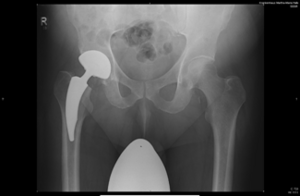

Beim Hüftgelenkersatz verwenden wir unterschiedliche Implantate inklusive der Kurzschaftprothese. Vorzugsweise werden diese, in Abhängigkeit der Knochenqualität, zementfrei eingebracht. Gelegentlich werden teilzementierte Prothesen, sehr selten vollzementierte Komponenten verwendet.

Röntgenaufnahme einer Hüftendoprothese, deutlich sichtbar im rechten Hüftbereich.

Kurzschafttotalendoprothese Hüfte

Röntgenaufnahme einer Hüftendoprothese im rechten Hüftbereich, deutlich sichtbar.

Teilzementierte Totalendoprothese Hüfte